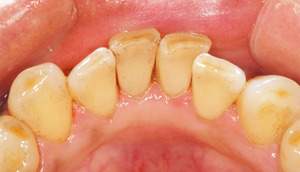

歯石除去

治療前

治療後

| 年齢 | 40歳・男性 |

| 主訴 | 歯石をとりたい |

| 治療内容 | 歯石除去 |

| 治療期間 | 30分 |

| 費用 | 約2,000円 |

| リスク・副作用 | ・歯ぐきの炎症が強いと歯石を取る際に出血することがあります。 ・処置後に歯がしみることがあります。 ・歯と歯の間に隙間ができるので、息が漏れ発音しにくいと感じることがあります。 ・歯ぐきの炎症が軽減すると歯ぐきが引き締まり、歯が長く見えることがあります。 |